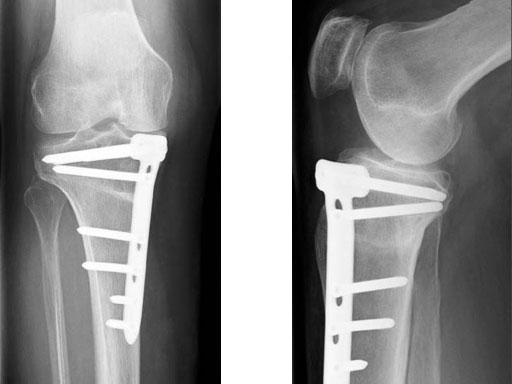

The correction is planned on a long-leg standing x-ray. After surgery, the mechanical axis should pass through a point 63% on the lateral side of the total width of the tibial plateau in the frontal plane. A transverse or slightly oblique incision is used to avoid damage to the saphenous nerve. The distal fibers of the medial collateral ligament are detached from the tibia. Under fluoroscopic control, two wires are placed in the proximal tibia marking the transverse osteotomy plane. The cut usually starts at the upper margin of the pes anserinus and ends at the tip of the fibula on the lateral side. The wires are placed exactly parallel to the tibial plateau thus taking into consideration the individual tibial slope of the patient. An incomplete cut of the posterior two-thirds of the proximal tibia is performed with an oscillating saw guided by the wires. Continuous irrigation avoids burn injury to the bone. A second osteotomy is now performed in the anterior third of the tibia in an angle of 100 ending above the patellar tendon insertion. A smaller saw blade is used and the complete anterior cortex is cut exactly in the frontal plane. The osteotomy is now gradually opened by inserting flat chisels or a spreader-chisel into the posterior osteotomy cleft. This process may take some minutes and can usually be completed without fracture of the lateral cortex. A bone spreader is now placed in the posteromedial edge of the tibia and the chisels are removed. The leg is extended and the correction is checked with the fluoroscope. A long metal rod is placed between center of the hip joint and center of the ankle joint. The projection of this rod should be at the planned point of correction on the tibial plateau lateral of the midline. Eccentric collapse of the medial joint space may cause accidental overcorrection. In this case pressure on the foot may simulate loading and body weight. The correction can be fine-tuned by opening or closing the spreader. The TomoFix Medial Tibia Plate is now placed in a subcutaneous pocket. The implant is precontoured and usually fits well to the bone surface. The distance holders avoid compression of the medial collateral ligament and the pes anserinus. Three proximal bolts are placed near the subchondral sclerosis zone. The position of the bolts is adapted to the anatomy of the proximal tibia giving optimum purchase for the bolts. An oblique lag screw is inserted distal to the osteotomy. This screw in the first combination hole allows careful compression of the lateral osteotomy hinge and pretensioning of the implant. A stab incision is created on the shaft and the implant is fixed monocortically with bolts. The lag screw and the distance holders are replaced by bolts. The medial collateral ligament is released longitudinally to reduce medial compartment pressure and the wound is closed in layers. An overflow drain may be used. Clinical and experimental work has proven that when this technique is closely followed, corrections up to and over 15 mm can be performed without bone grafting or use of bone substitutes.

A 68-year-old female.

Case provided by Alex Staubli, Luzern, CH